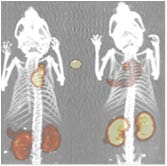

PET-CT imagePositron Emission Tomography (PET) provides unique in vivo information about specific molecular pathways in cancer, and holds great translational value for Hillman investigators. Preclinical imaging with PET and/or PET-CT:

• provides noninvasive small animal imaging of molecular targets using dedicated small animal PET with optional co-registration of CT

• facilitates translational research aimed at imaging cancer patients with clinical PET-CT